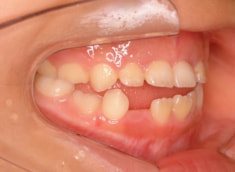

治療前